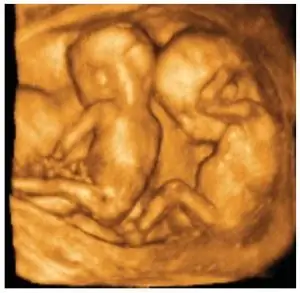

The Womb-Mates Я всегда хотел быть близнецом, но у меня никогда не получалось. Я не могу представить, как здорово было бы иметь приятеля матки с рождения.

Эти увлекательные 3D-фотографии близнецов в утробе матери взяты из исследования международного научного журнала Jaypee. Разве ты не чувствуешь любовь, просто глядя на их объятия?